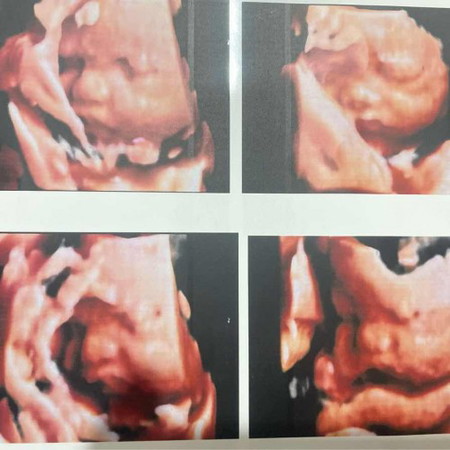

31+4 น้ำหนักลูก 2,100

มีแม่ๆบ้านไหน คลอดเดือนมิถุนายน น้ำหนักลูกเท่าไหร่บ้างแล้วค่ะ ##ขอบคุณสำหรับคำตอบค่ะ